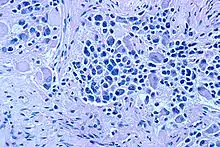

| Microscopic view of a typical neuroblastoma with rosette formation | |

On microscopy, the tumor cells are typically described as small, round and blue, and rosette patterns (Homer Wright pseudorosettes) may be seen. Homer Wright pseudorosettes are tumor cells around the neuropil, not to be confused with a true rosettes, which are tumor cells around an empty lumen.[28] They are also distinct from the pseudorosettes of an ependymoma which consist of tumor cells with glial fibrillary acidic protein (GFAP)–positive processes tapering off toward a blood vessel (thus a combination of the two).[29] A variety of immunohistochemical stains are used by pathologists to distinguish neuroblastomas from histological mimics, such as rhabdomyosarcoma, Ewing's sarcoma, lymphoma and Wilms' tumor.[30]

Neuroblastoma is one of the peripheral neuroblastic tumors (pNTs) that have similar origins and show a wide pattern of differentiation ranging from benign ganglioneuroma to stroma-rich ganglioneuroblastoma with neuroblastic cells intermixed or in nodules, to highly malignant neuroblastoma. This distinction in the pre-treatment tumor pathology is an important prognostic factor, along with age and mitosis-karyorrhexis index (MKI). This pathology classification system (the Shimada system) describes "favorable" and "unfavorable" tumors by the International Neuroblastoma Pathology Committee (INPC) which was established in 1999 and revised in 2003.[31]